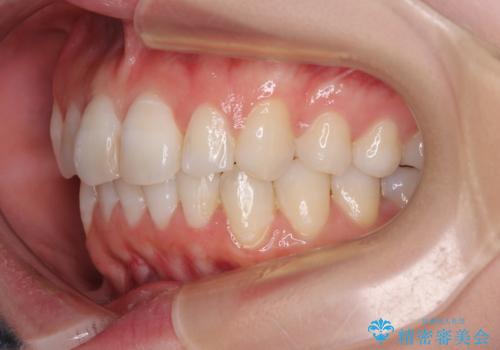

- 上下前歯のデコボコを改善したいとのことで来院された患者様です。

マウスピースを長時間装着し続ける自信はあまりないとのことでしたが、目立たない装置であれば頑張って装着するとのことで、インビザラインによる矯正治療を行うこととしました。

初めの1年くらいは何とか頑張って装着してくださいましたが、途中から変化をあまり感じられなくなり、日々の装着時間は徐々に短くなってしまいました。

前歯のデコボコはもっと改善できましたが、3年半が経過し、初診時と比べたら大幅に良くなったとのことで終了することとなりました。